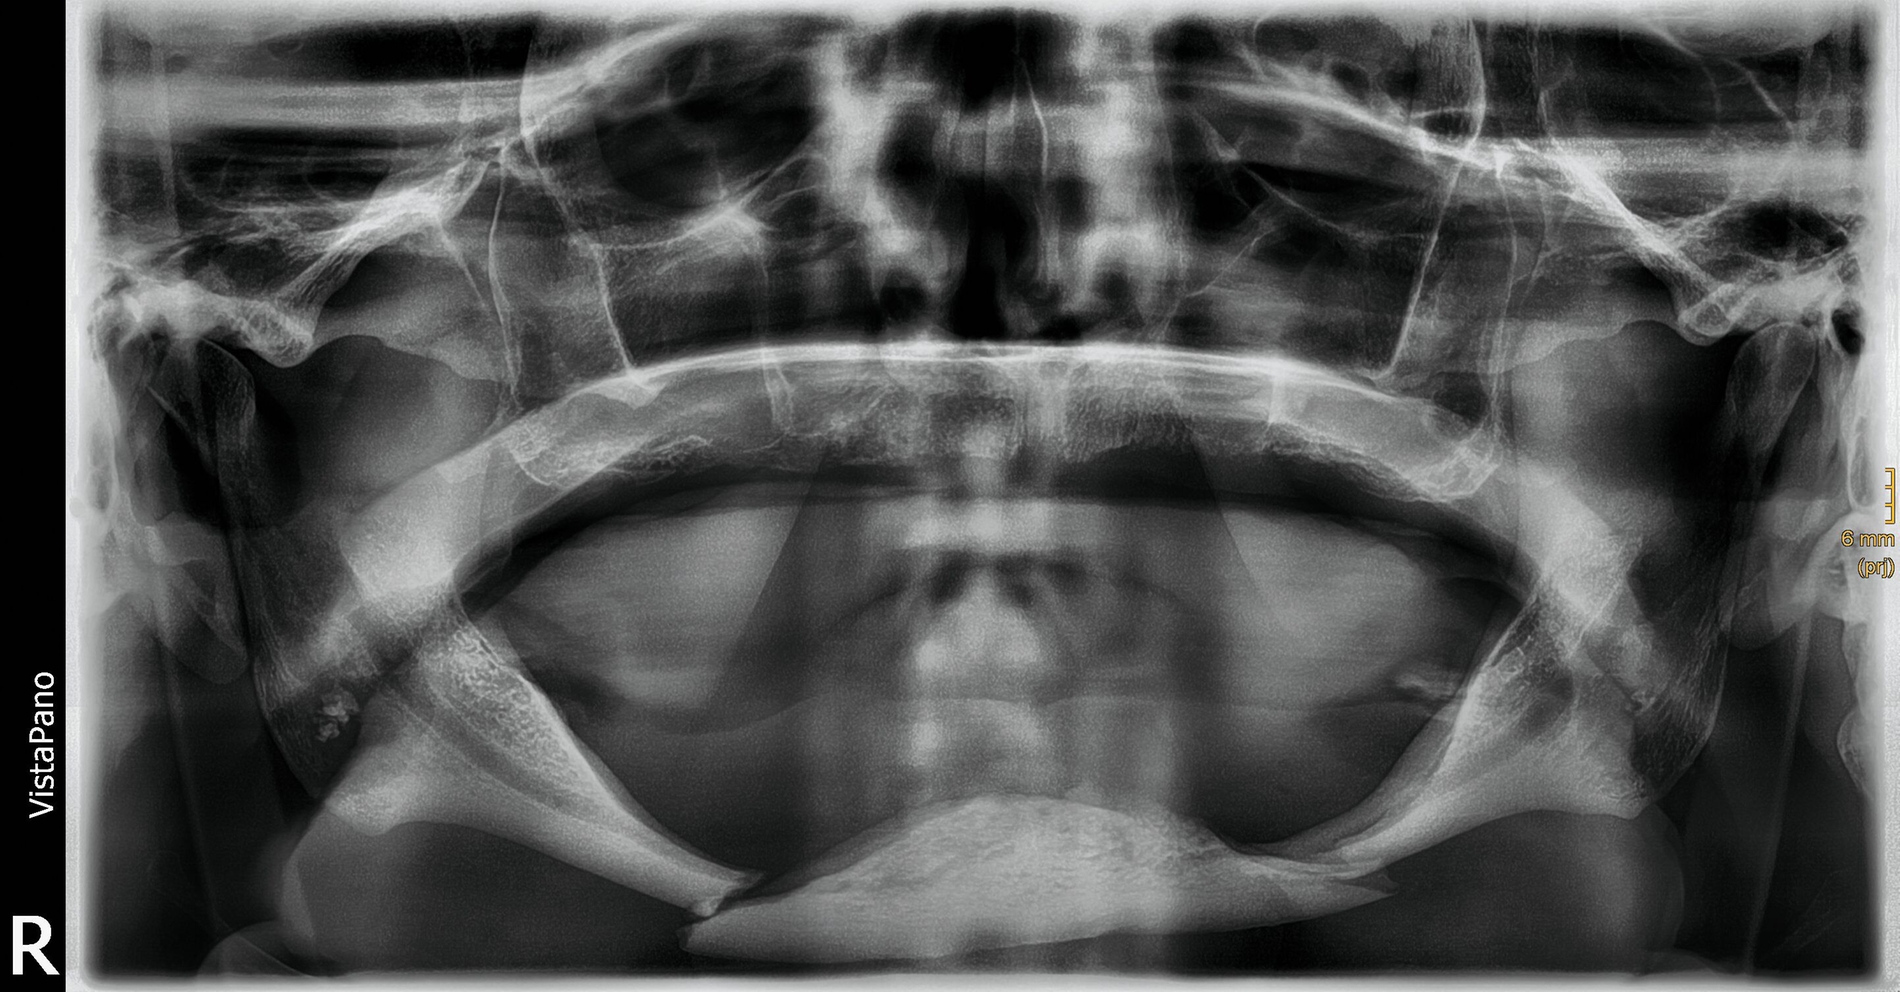

Durch den Rettungsdienst wurde dem Universitätsklinikum Freiburg ein 75-jähriger Patient zugewiesen. Er war aus etwa einem Meter Höhe von einer Leiter gestürzt. In der Notfalldiagnostik mittels Computertomografie (CT; Polytraumaspirale) wurden eine komplexe doppelte Unterkieferkorpusfraktur bei atrophem Unterkiefer (Pencil bone fracture) sowie eine Beckenringfraktur vom Typ Tile B diagnostiziert.

Während die Klinik für Orthopädie und Unfallchirurgie ein konservatives Versorgungsregime mit 20 kg Teilbelastung über sechs Wochen zur Behandlung der Beckenringfraktur empfahl, planten wir in der MKG-Chirurgie die operative Frakturversorgung des stark atrophierten und disloziert frakturierten Unterkiefers. Der während der Notfalldiagnostik erstellte CT-Datensatz wurde auf eine Voxelsize von 0,6 Millimetern zurückgerechnet und in einem dafür entworfenen und zertifizierten Forum eines externen Unternehmens zur weiteren Bearbeitung hochgeladen.

Bei zahnlosem Ober- und Unterkiefer erfolgte die virtuelle Repositionierung des frakturierten Unterkiefers (Abbildung 2a). Mittels CAD/CAM-Verfahren wurde eine stabile Rekonstruktionsplatte aus Titan (patientenspezifisches Implantat; PSI) geplant und hergestellt. Dabei sollte die Position des PSIs im Bereich des Unterkieferkorpus weit kaudal an der Basis sein, so dass später bei der Anpassung einer neuen Unterkieferprothese keine Interferenzen auftreten (Abbildung 2b).